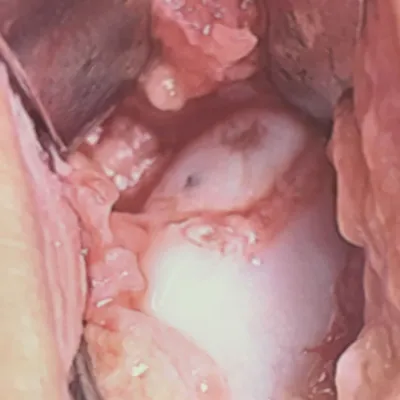

Intraop arthroscopic pics of talar OCD surgery.

The osteochondral fracture can be seen and it is loose. We are measuring the size on the last 2 pics.

After fixating with an absorbable pin and K-wire.